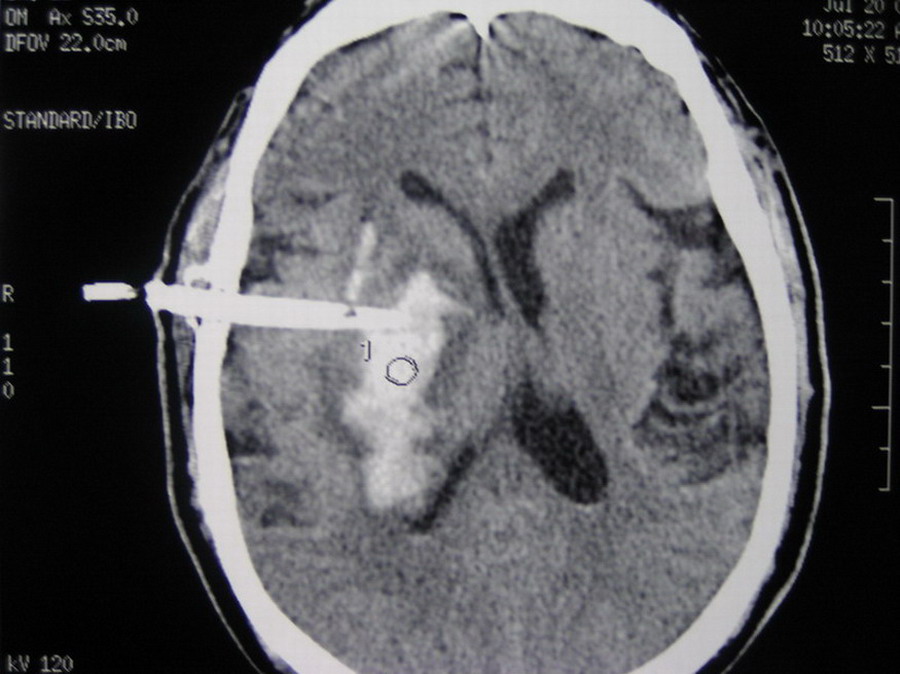

以下是引用13081830109在2007-4-3 22:44:00的发言:[br]感觉1:穿刺针为非专用的 不知是哪里生产的有专利证吗? [br] 2:穿刺点选择的往下了 该位置易引起继发性血肿[br] 3: 穿刺角度选择的往后了[br] 4: 侧孔位置不对 该位置在冲洗时极易抽出脑组织[br] 建议: 旋转穿刺针使侧孔向后方[br] 冲洗时用小注射器(5ml)以0.5压力为好[br] 尿激酶应用要慎重[br] 如患者病情允许不要用脱水药[br] [br][br][br][br]以上意见仅供参考[br]